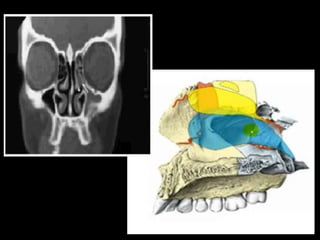

• Senos paranasales

Paranasales

(desembocan)

• Atico : desemboca las celdas o senos

esfenoidales.

• Meato superior: desemboca las celdas

etmoidades posteriores

• Meato medio e infundíbulo : desemboca las

celdas etmoidales anteriores , senos frontales

, senos maxilares .

• Meato inferior : conducto lacrimo nasal